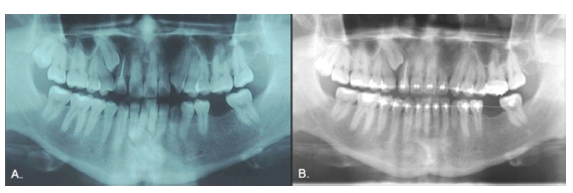

Case 7

Female, 16 years of age. The 1.5, 2.1, 3.5, 4.3, and 4.5 teeth were missing, and the inferior right primary canine and two primary second molars were still present (Fig. 13). The radiograph showed that the 4.3 was in type 1 transmigration, the 1.5, 3.5, and 4.5 exhibited agenesis, and the 2.1 was impacted and had an associated supernumerary tooth (Fig. 14A). The simultaneous presence of supernumeraries and agenesis is a very rare (0.33%) condition known as concomitant hypo-hyperdontia (14). As in Case 6, the 4.3 was near the roots of neighboring teeth and the CBCT revealed a lesion that extended from the right deciduous canine to the left lateral incisor, almost as if showing the path that the transmigrated canine had followed (Fig. 14, B-D), so it was extracted. The 2.1 was surgically exposed and a post attached to it to allow its movement with orthodontics. The gap for the 1.5 was to be closed using orthodontics, but the spaces for the inferior premolars were to be maintained for later rehabilitation with dental implants (Fig. 15).